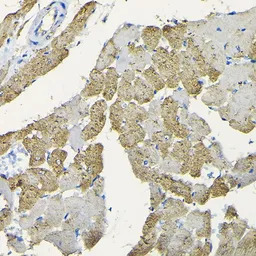

IHC-P analysis of rat heart tissue using GTX64490 HSP22 antibody.

Dilution : 1:100